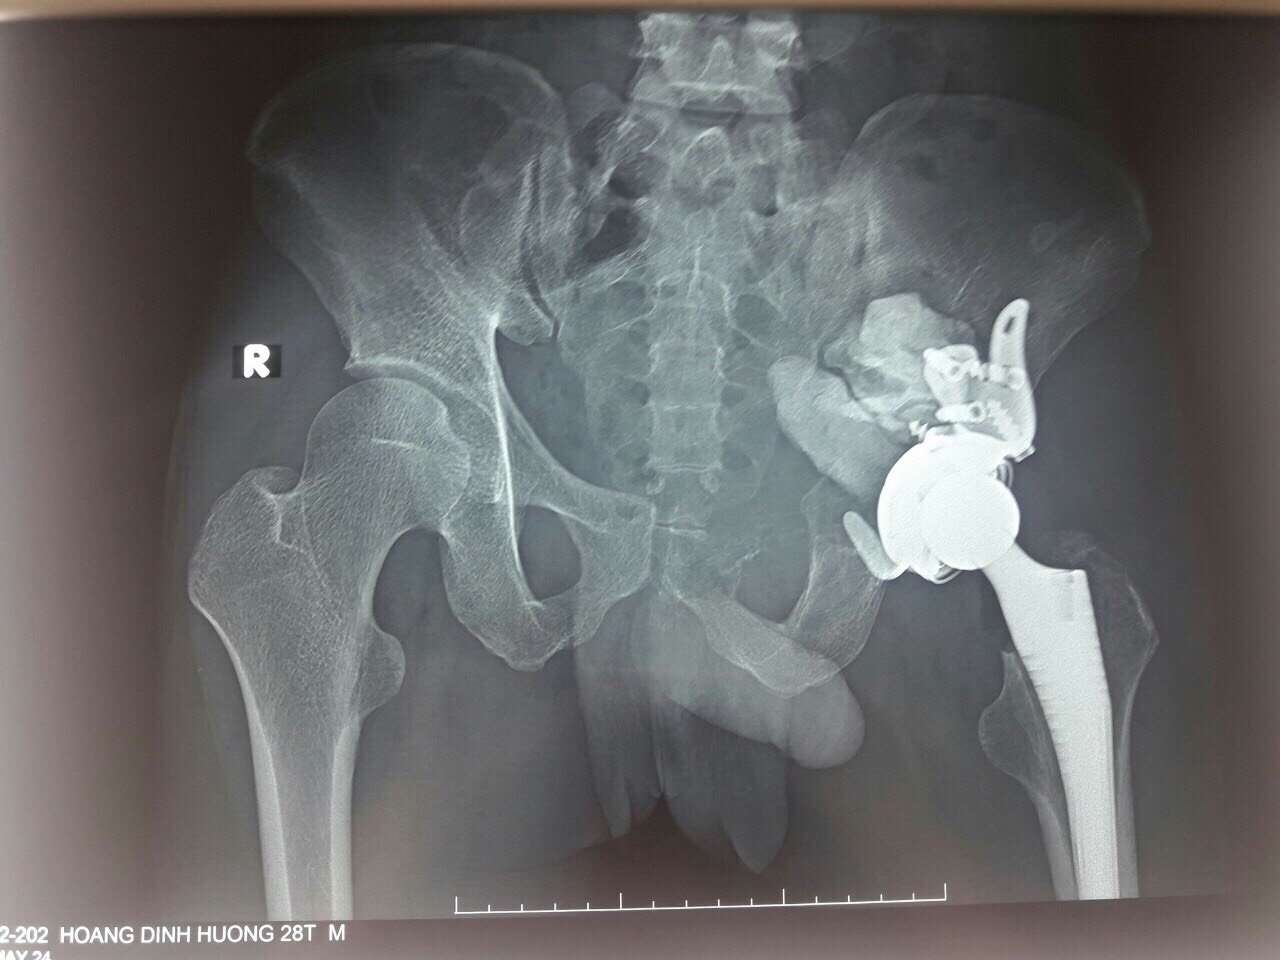

Phim chụp Xquang của anh H. sau ca phẫu thuật cho thấy khớp háng được tạo hình lại (Ảnh: BVCC)

Đường mở vào ổ bụng qua đường trắng giữa dưới rốn, kiểm soát bó mạch chậu trong, loại bỏ trọn vẹn khối u, làm sinh thiết tức thì đánh giá đảm bảo triệt để, cầm máu kỹ và sử dụng xi măng sinh học để phục hồi một phần khuyết xương cánh chậu và ổ cối.

Cùng với đó, các bác sĩ lựa chọn phương án tạo hình lại khớp háng với khớp háng nhân tạo có sử dụng rọ ổ cối để cố định ổ cối nhân tạo lên cả phần cánh chậu lành. Kíp phẫu thuật kiểm tra kỹ, đặt dẫn lưu và phục hồi giải phẫu của bao khớp và phần mềm.

Sau 6 giờ đấu trí cam go, ca phẫu thuật đã diễn ra thành công, khối u được lấy bỏ triệt để, không có tai biến tổn thương thần kinh, khớp háng được phục hồi bằng khớp háng nhân tạo giúp cho bệnh nhân có thể tập luyện dần trở lại.